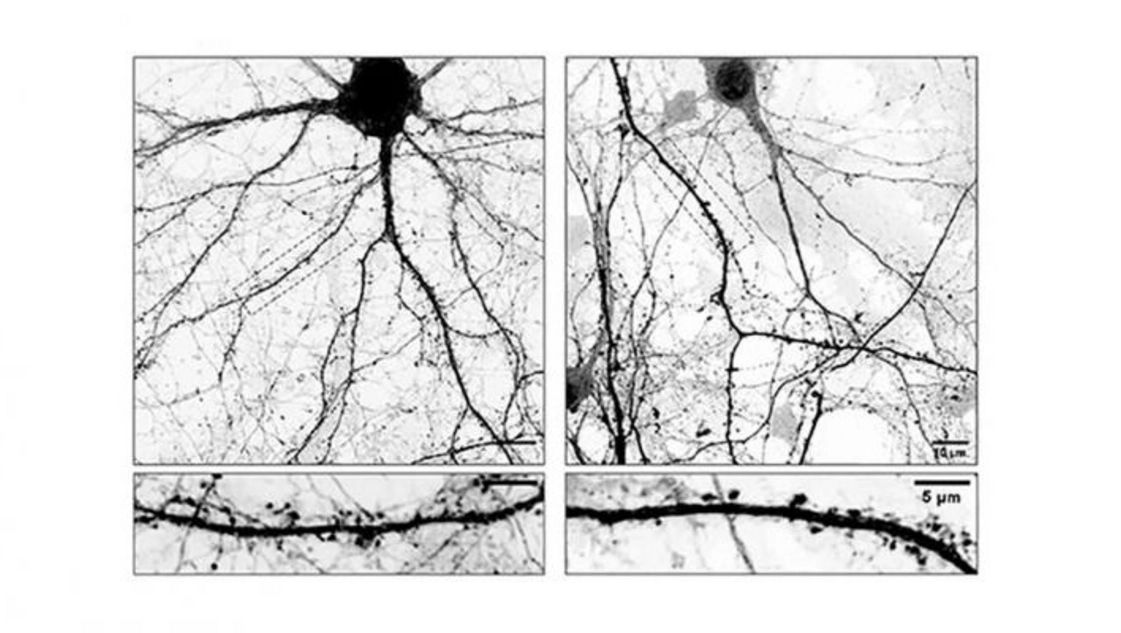

Los científicos descubrieron que L-Dopa puede incorporarse a los microtúbulos que forman parte del esqueleto interno de las neuronas. Estos microtúbulos funcionan como “rieles” microscópicos que permiten el movimiento interno de sustancias esenciales y tienen un papel crucial en el mantenimiento de la conexión entre las neuronas (sinapsis). “El problema es que cuando L-Dopa se integra en estos microtúbulos los hace menos dinámicos afectando su ingreso a las espinas dendríticas, estructuras que funcionan como las ‘antenas’ receptoras de la neurona donde se forman las sinapsis. Como consecuencia directa de esto, las neuronas comienzan a perder espinas, claves para la comunicación neuronal. Entendemos que esta inestabilidad sináptica podría explicar algunas de las complicaciones que aparecen luego de un tiempo prolongado de tomar L-Dopa”, señala Gastón Bisig, investigador del CONICET.